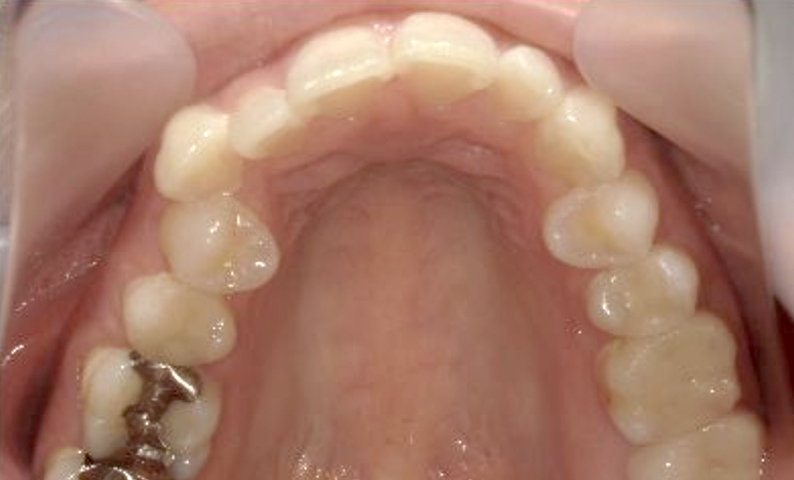

症例_002 上顎だけの部分矯正

治療期間:7ヶ月金額:30万円+税女性前歯のガタガタ上の前歯だけ

| Before | After |

|---|---|

|